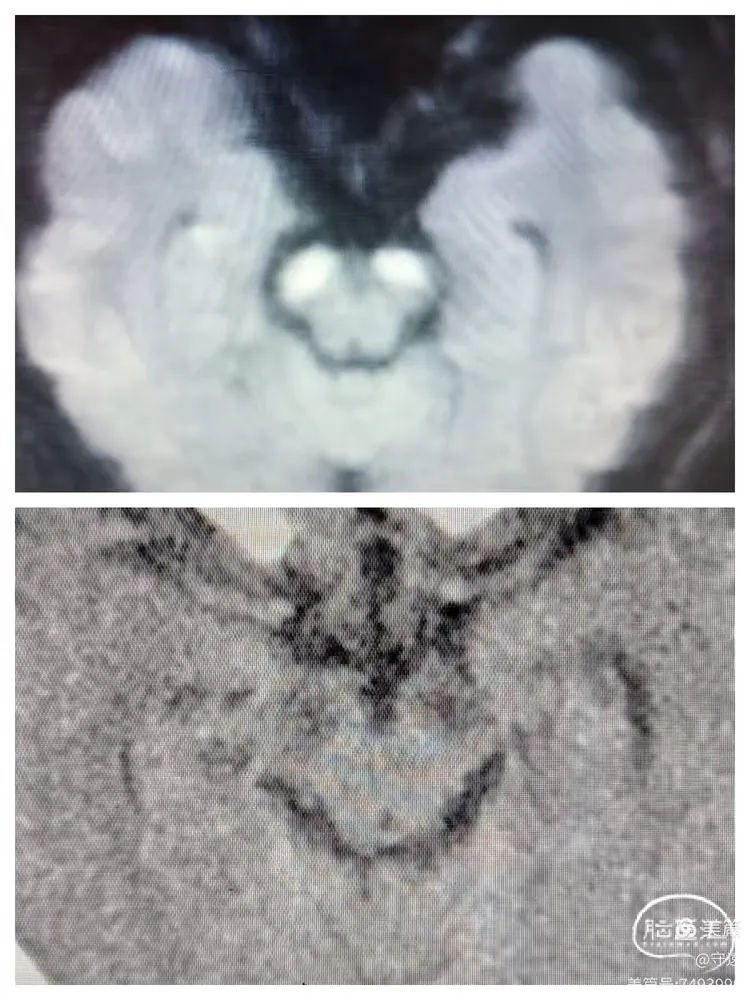

核磁显示:双侧桥臂,右侧丘脑梗塞。

DwI示双侧桥臂高密度影

右侧丘脑梗塞

术前核磁与术后12小时CT检查对照